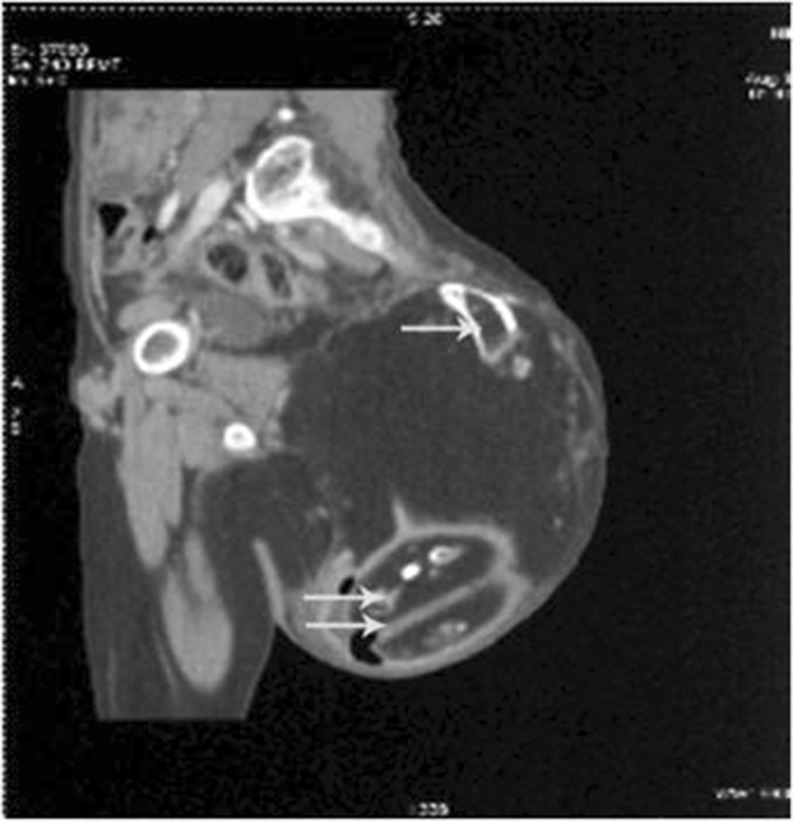

An 11-year-old girl presented with a mass in the left gluteal region, which was noticed at birth and slowly grown to the present size. She limped while walking. The mass was 25 cm in maximum dimension with stretched-out skin on surface. It was nontender, extending just beyond midline, vertically up to the left iliac crest and hanging over the gluteal fold up to the upper third thigh. It was partially fixed to underlying structures. Computed tomographic (CT) scan showed the mass with a variable density pattern along with presence of long bone and foot development with suggestion of fetiform teratoma (Fig. 1). The lesion was excised in toto. Peroperatively, it was mainly in the subcutaneous and submuscular plane under gluteus maximus, attached to the sacrum via fascia only, so the sacrum bone was spared from excision but with removal of coccyx. Two-year follow-up had been uneventful.

Fig. 1.

Computed tomographic (CT) scan showing a mass in left presacral region, extending up to iliac crest with a variable density pattern and presence of long bone (arrow) and foot development (double arrow)